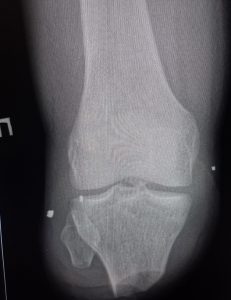

From the first days we started to provide assistance to wounded civilians and the military from different parts of our country. Our work is to diagnose various injuries of the chest, abdomen, skull, pelvis and especially the limbs. We help thoracic, abdominal and facial surgeons, ophthalmologists, and especially orthopaedists in preoperative and postoperative stages of the treatment.

One of our tasks, as radiologists, has been to find foreign bodies in the people’s arms, legs, abdomen and thoracic wall with help of radiography or ultrasound. We also help in finding traumatic injuries to internal organs. Despite of lack of a new equipment we try to help all our patients as much as it possible. Psychological support of patients is also important in our work which I am are doing.

The X-ray in the Figures in this article are of one of our civilian patients who has recently lost one of his hands, one leg and damaged other leg after the Russians came to his village in the south of Ukraine.